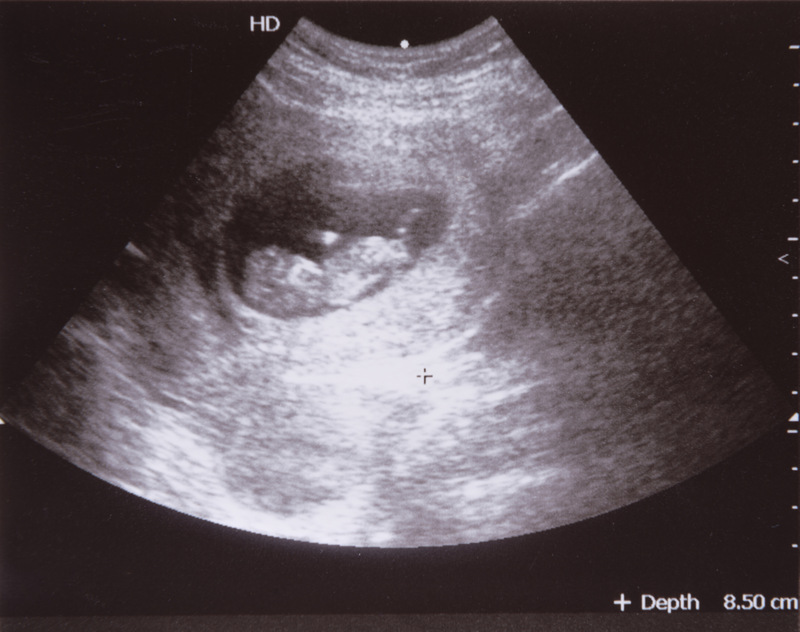

早期流產(chǎn)的主要原因中,胚胎和胎兒染色體異常是主要原因,約占50~60%,對(duì)于這部分流產(chǎn),我們都知道,遵循自然界優(yōu)勝劣汰的結(jié)果,我們補(bǔ)充再多的黃體酮也無(wú)益,所以對(duì)于初次妊娠先兆流產(chǎn)者,多考慮自然淘汰所致,無(wú)需進(jìn)行過于積極的治療。目前的保胎指證還是依據(jù)先兆流產(chǎn)的變現(xiàn),如有停經(jīng)史、陰道出血、有或無(wú)腹痛、子宮大小和停經(jīng)孕周相符、超聲提示宮內(nèi)孕的情況下,對(duì)孕酮水平低者可以進(jìn)行孕激素(黃體酮)治療。